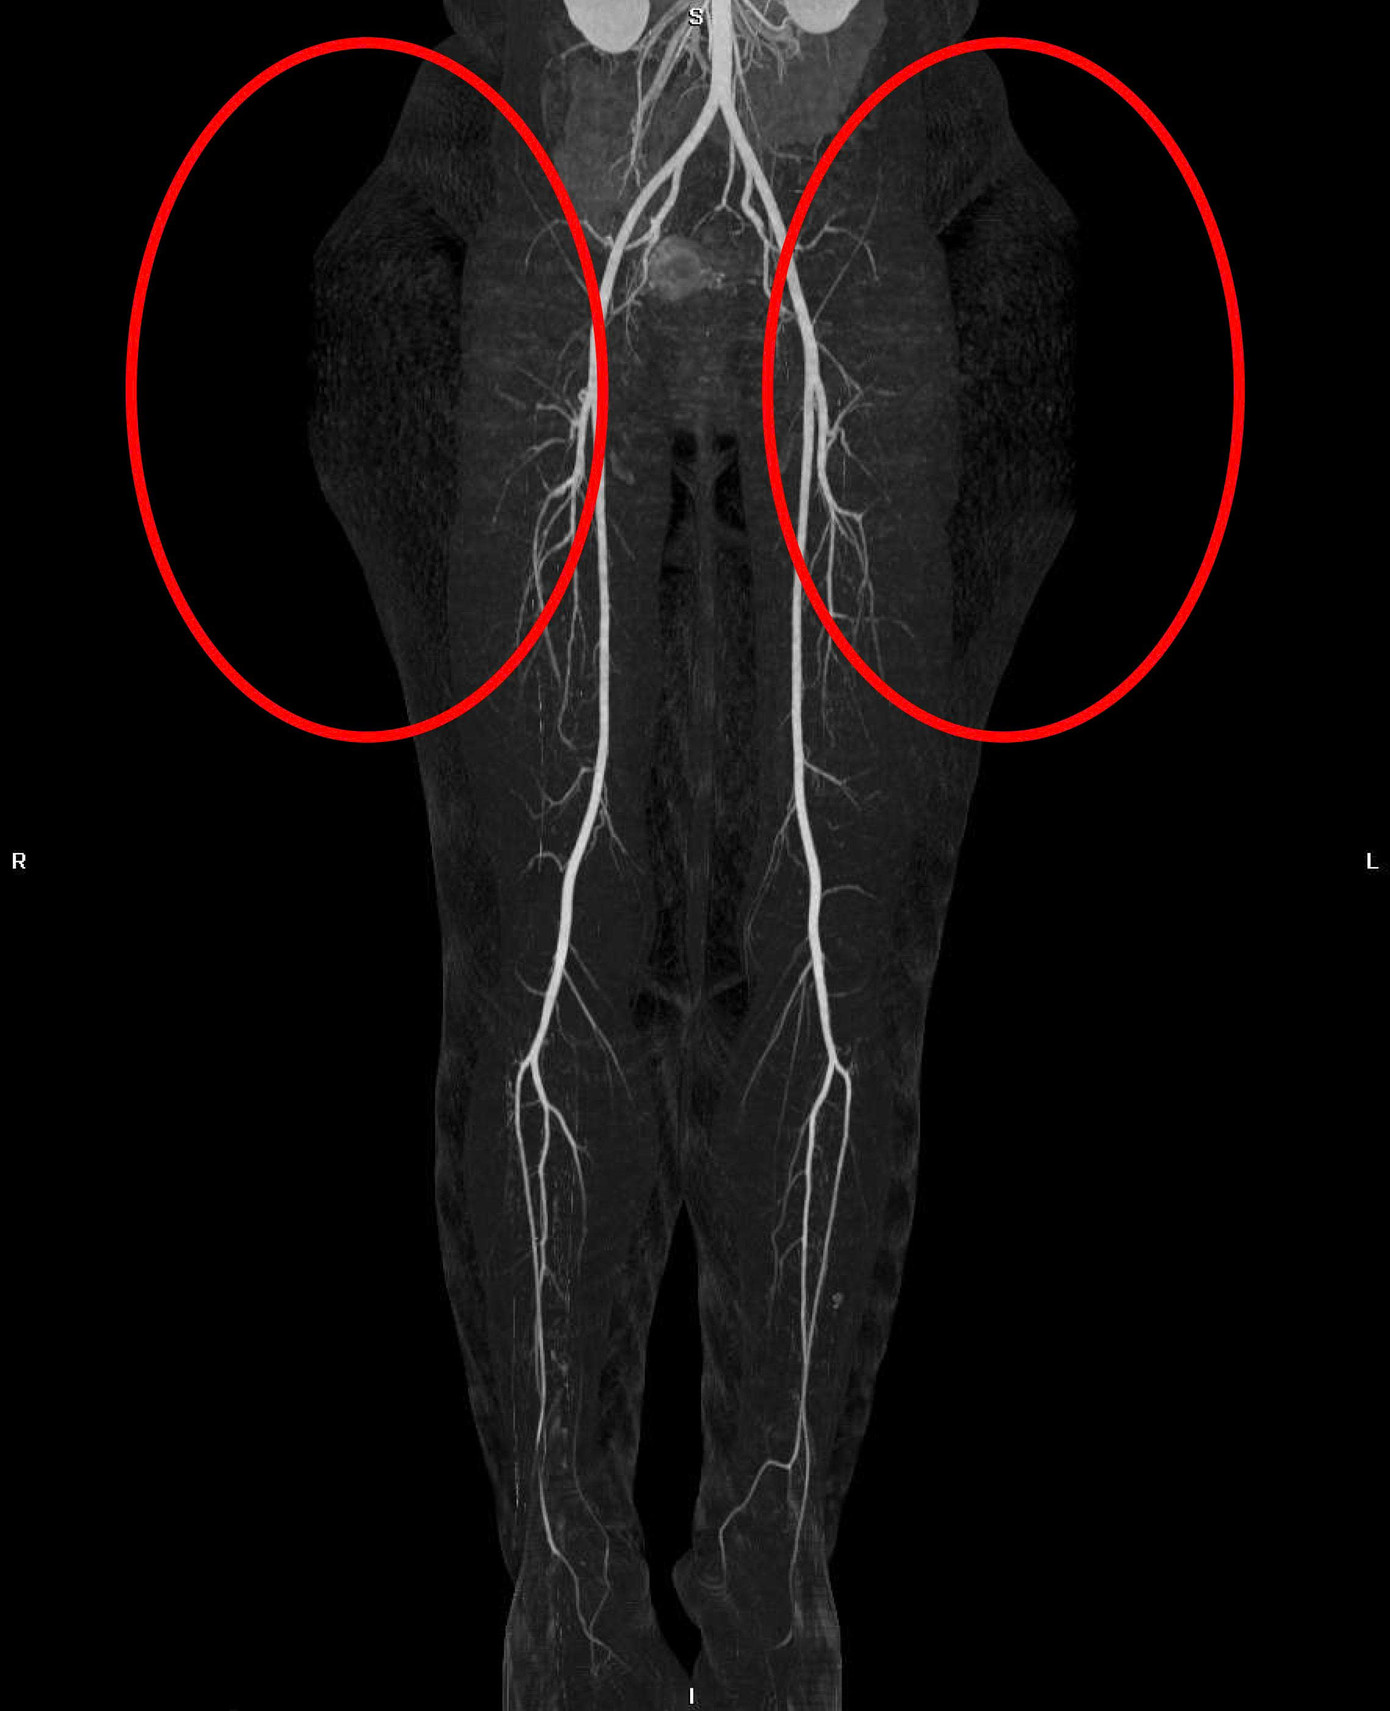

| Hình ảnh kiểm tra ghi nhận 2 khối mỡ đối xứng ở vùng mông của nữ bệnh nhân |

Dạng bệnh lý mỡ đối xứng (Multiple Symmetric Lipomatosis – MSL), khu trú bất thường tại vùng mông. Đây là vị trí rất hiếm gặp, bởi bệnh thường xuất hiện ở vùng cổ, vai, chủ yếu ở nam giới trung niên nghiện rượu. Trong khi đó, bệnh nhân là nữ, trẻ tuổi, không có yếu tố nguy cơ điển hình.

Hình ảnh chẩn đoán cho thấy mô mỡ lan rộng, không có bao vỏ, bám sâu vào cân cơ, khiến việc điều trị bằng ăn kiêng hay tập luyện hoàn toàn không hiệu quả.

Bệnh nhân được chỉ định phẫu thuật bóc tách khối mỡ khổng lồ (bên trái 10x27x27cm, bên phải 10x25x28cm) kết hợp tạo hình vùng đùi – mông. Ca phẫu thuật kéo dài hơn 6 giờ do TS.BS Tú Dung thực hiện, sử dụng dao mổ siêu âm để bóc tách chính xác, bảo tồn mạch máu, thần kinh, đồng thời phục hồi đường nét hình thể.